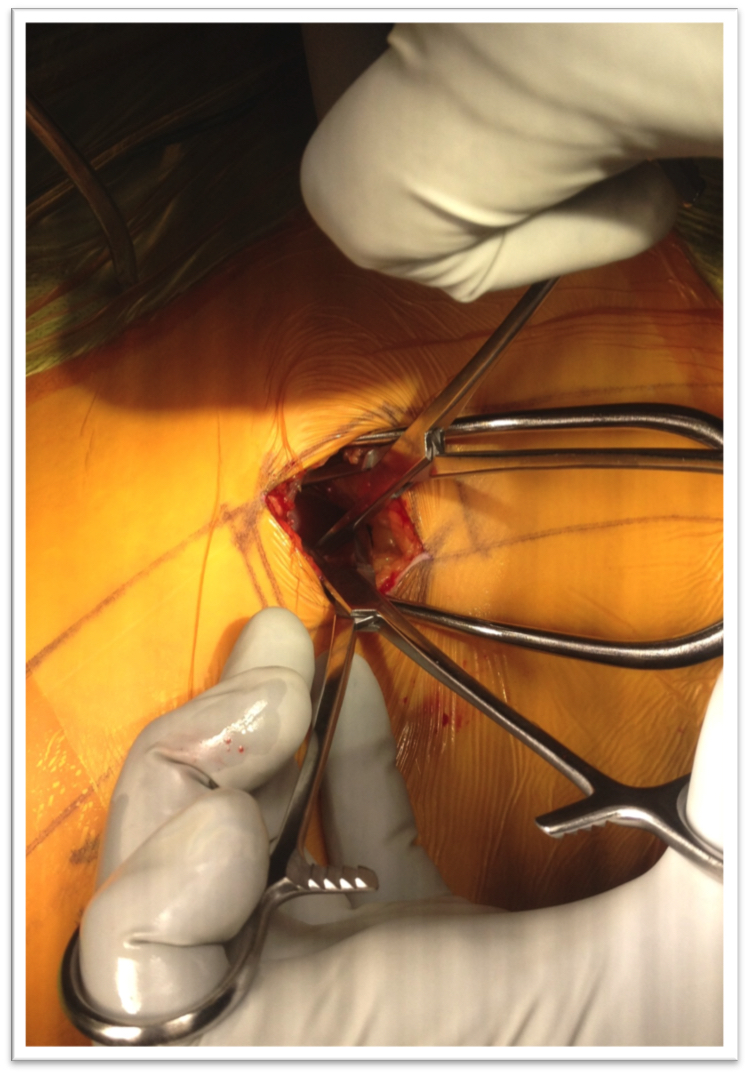

Descargas

6. Berjano P, Gautschi OP, Schils F, Tessitore E. Extreme lateral interbody fusion (XLIF®): how I do it. Acta Neurochir (Wien) 2015;157(3):547-51. doi: 10.1007/s00701-014-2248-9